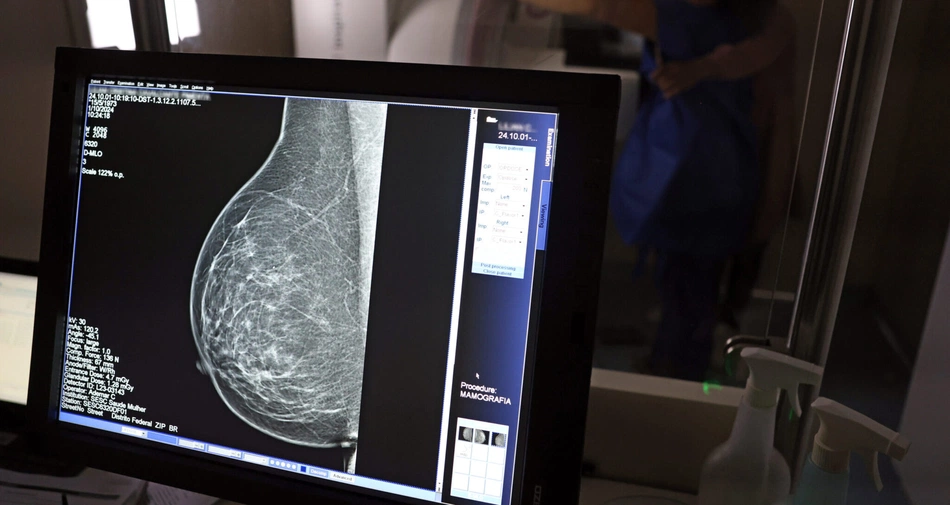

Piauí realiza 57 mil mamografias e recebe 224 medicamentos para câncer de mama

No ano de 2025, o Piauí conquistou números significativos no acesso ao diagnóstico precoce do câncer de mama. Com 43 mamógrafos fixos e o serviço itinerante dos Caminhões da Mamografia, o estado contabiliza mais de 57 mil mamografias realizadas apenas em 2025; a Trastuzumabe Entansina, utilizada para tratar o câncer de mama, foi recentemente incorporada ao Sistema Único de Saúde (SUS).

Com foco principal em mulheres entre os 40 e 49 anos, a faixa etária passou a ser atendida, seguindo a nova orientação do Ministério da Saúde, sob demanda. Já as 224 unidades do medicamento, recebidos nessa quinta-feira (23), é usado no tratamento daqueles casos mais agravados do câncer de mama.

Com a chegada do primeiro lote do Trastuzumabe Entansina, utilizado para casos de câncer de mama HER2-positivo, o Piauí disponibilizará o medicamento conforme os protocolos clínicos vigentes. Com isso, a mortalidade das pacientes pode ser reduzida em até 50%.

A orientação do ministro da Saúde, Alexandre Padilha, é de as mulheres de 50 a 74 anos façam mamografia pelo menos a cada dois anos. Ele acrescenta ainda que: “se uma mulher a partir dos 40 anos quiser fazer o exame, o profissional deve garantir o acesso”.